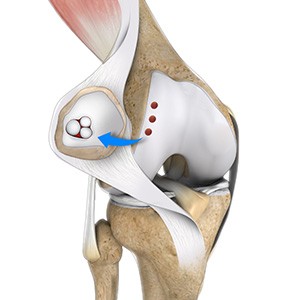

Meniscus Collagen Implant

A meniscus collagen implant is a biocompatible scaffold that is made of highly purified collagen which helps to reinforce a damaged knee meniscus and promote the growth of new tissue. The implant has the same shape as the human meniscus and can be trimmed by the surgeon to fit the size of the defect in the damaged meniscus.